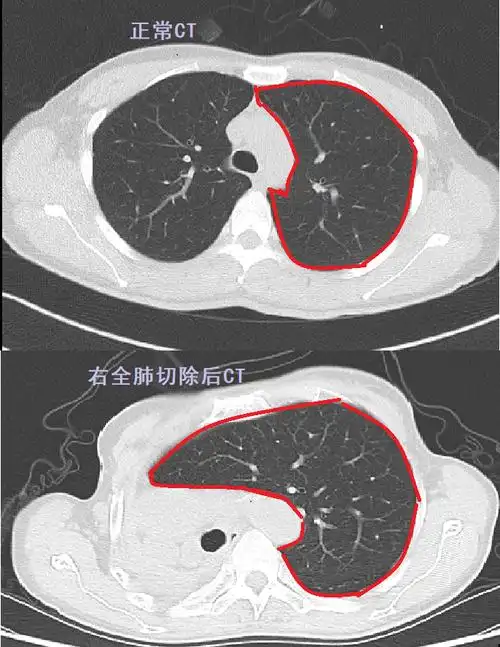

肺切除术后ct对比.png